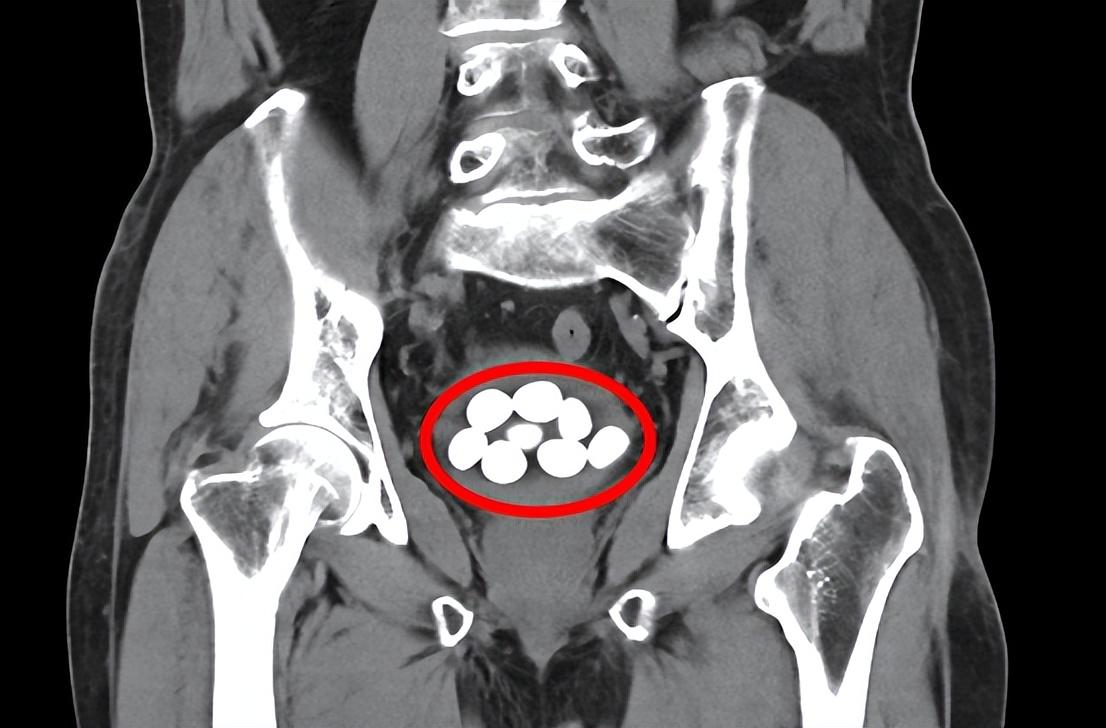

85歲老人9顆膀胱結石分別擊碎取出

平南縣第二人民醫(yī)院泌尿外科為一位85歲老人成功實施經尿道膀胱結石碎石術和前列腺電切手術,將9顆膀胱結石分別擊碎取出,解除了老人的病痛之苦。整個手術持續(xù)近2個多小時,術后第四天,經泌尿外科??谱o理團隊的精心護理,患者順利出院。